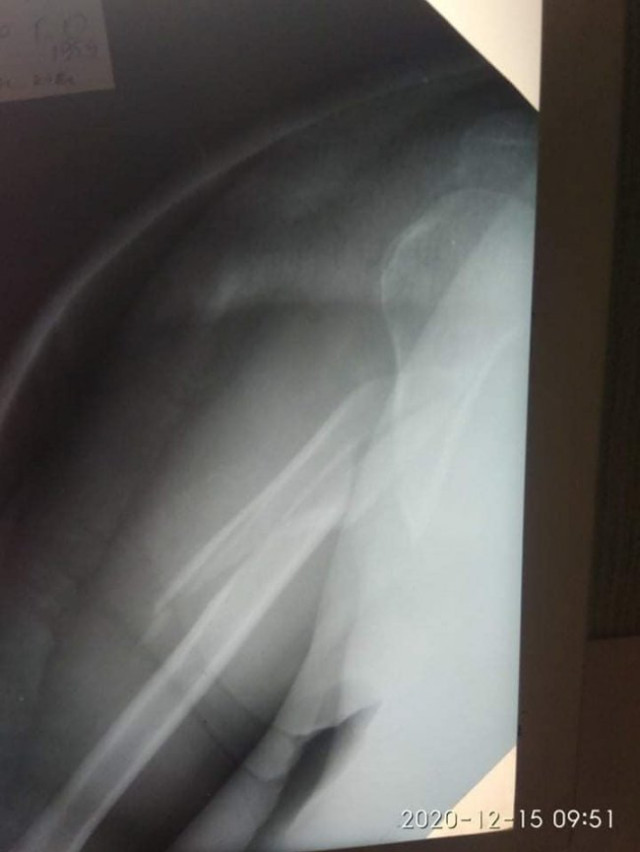

«Ця травма виявилась надскладною і з поганим подальшим прогнозом для якості життя пацієнтки.

Діагноз: Закритий багатовідламковий перелом діафізу правої плечової кістки», – йдеться в дописі.

60-річній жінці загрожувала повна втрата функцій правої руки. Вона розповіла, що травму дістала у побуті.